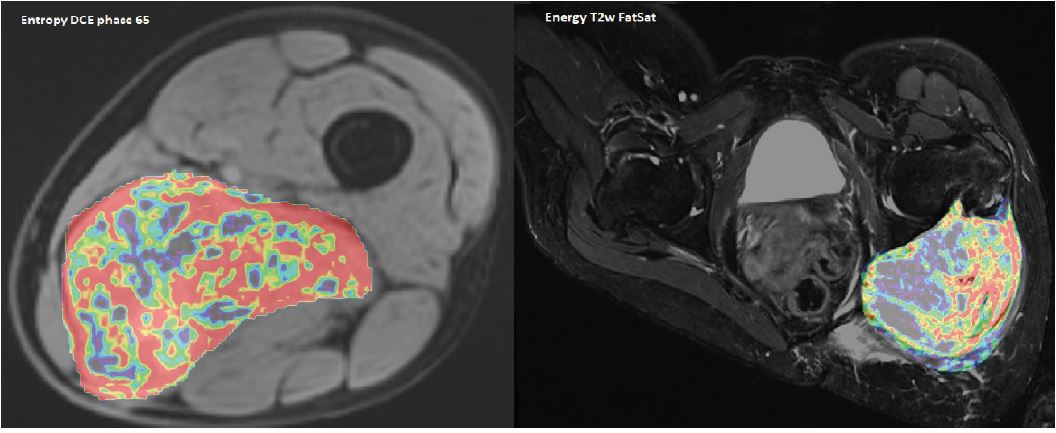

Радіоміка та аналіз текстури також дозволяють кількісно визначити неоднорідність тканини; з можливістю значного прогресу в прогнозуванні еволюції цих пухлин. Аналіз текстури дає змогу отримати понад сотню параметрів текстури з цікавого регіону чи обсягу (рис. 5). Ці потенційні нові біомаркери, консолідовані за допомогою штучного інтелекту, дозволяють автоматично сегментувати різні частини цих пухлин. Таким чином, радіолог може легко кількісно визначити ділянки посилення або некрозу та порівняти їх зміну на різних етапах лікування.